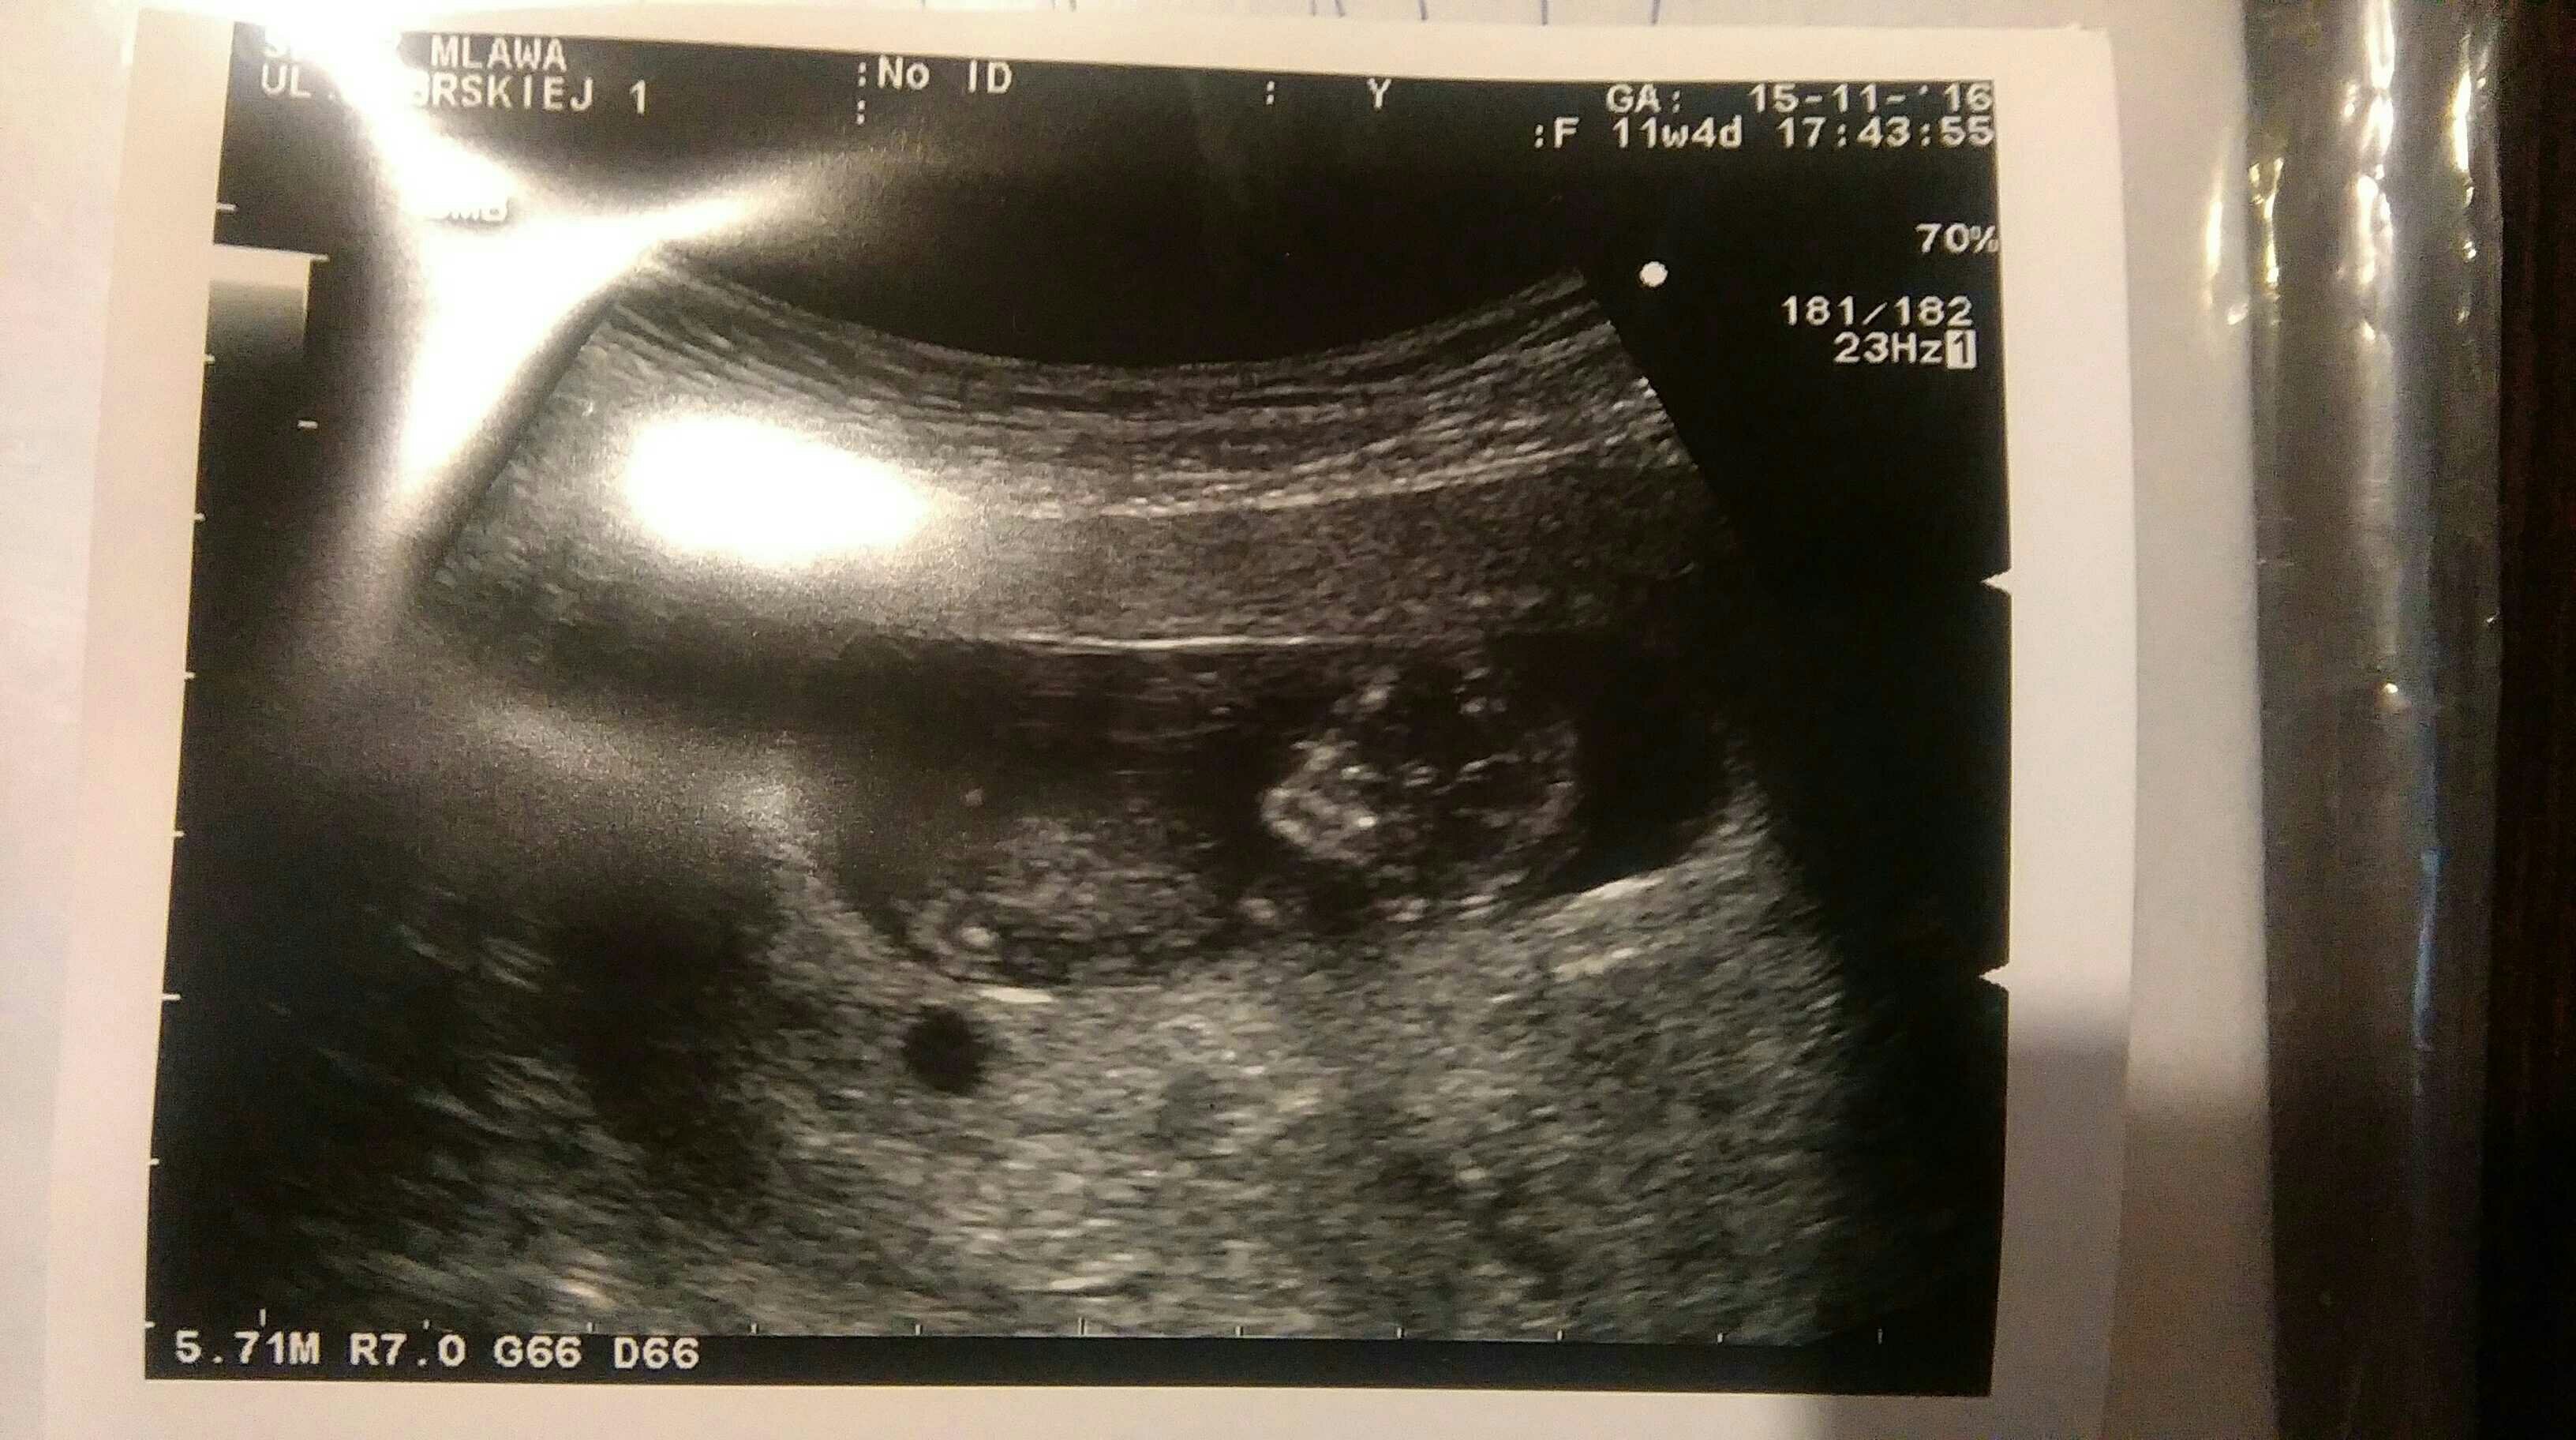

Dziewczynki ja już po USG. Dzidziuś zdrowy! Parametry IDEALNE, kość nosowa: JEST, przezierność: 0,9. To był miód na moje uszy [emoji7] Widziałam jak się rusza, był odwrócony pleckami. Maluszek wyszedł idealnie: z USG i OM tyle samo! Poprosiłam o jedną fotkę dzidziusia, żeby pokazać chłopcom i dobrze że to zrobiłam bo dołączyła tylko paramerty. Zobacz załącznik 783030 Jestem mega szczęśliwa, jem kebaba i pije turecką herbatkę z imbirem u znajomego który dla mnie robi miksy swoich potraw (wedle zachcianki hihi)

Edit: drugi pęcherzyk nadal jest, nie rośnie, nie rozwija się. Teraz to po prostu torebka z płynem do monitorowania.